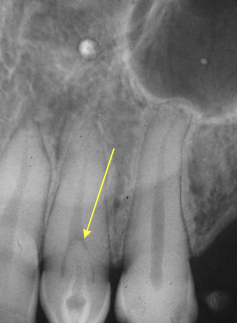

nonhereditary developmental anomaly, most common in max ant teeth, usually involves one quadrant, very large pulps with minimal dentin and enamel

regional odontodysplasia “ghost teeth”

what is the diagnosis?

regional odontodysplasia